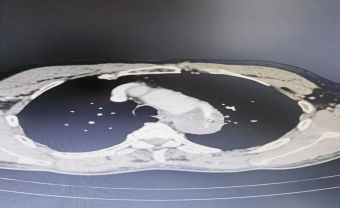

第二,开展新技术新业务,填补彭水县的医疗领域的空白。与彭水血管外科团队通力合作,先后开展了主动脉夹层腔内隔绝术,肺动脉造影吸栓术各1例,手术效果良好,患者均已康复出院,回访患者恢复良好。

典型病例资料1: